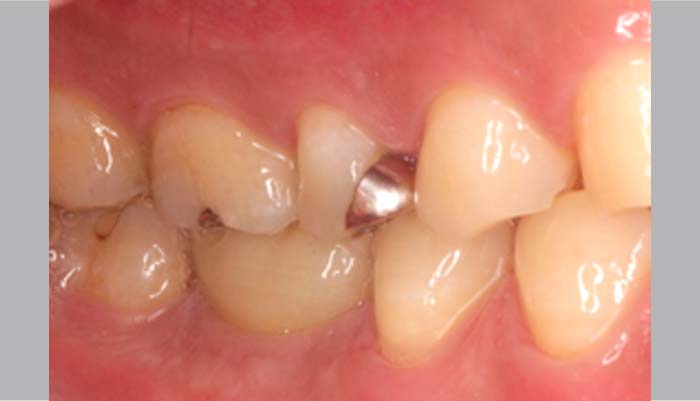

症例紹介